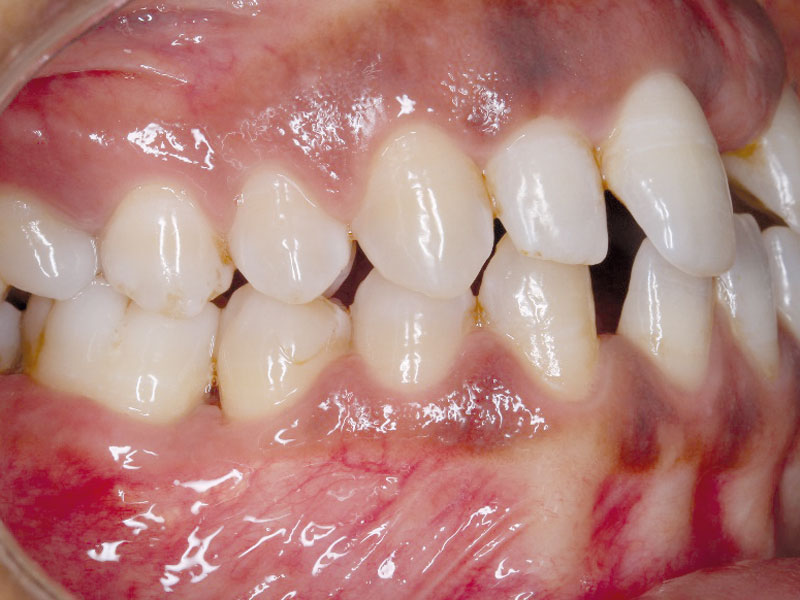

01/08 - PPD of 9mm at mesial of LR6Regeneration at LR6 with cerabone® and collprotect® membrane using simple papilla preservation technique - Dr. D. Chatzopoulou